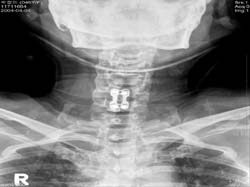

<ô¼ö

¼Õ»ó ÈÄ ¼ö¼ú °á°ú>

¼Õ»ó ȯÀÚÀÇ MRI>